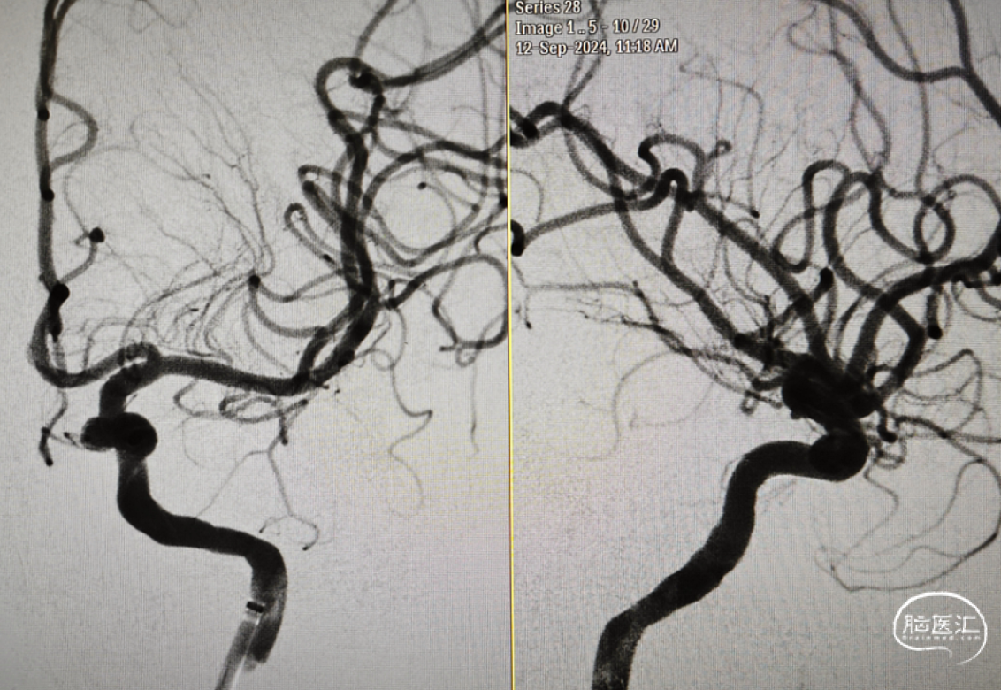

术后即刻造影